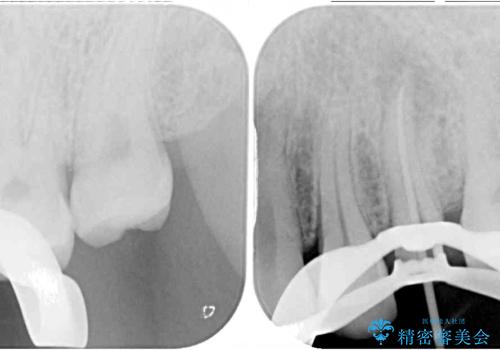

診査の結果、既に歯の神経は失活しており、レントゲンより根尖部に病変を認めました。

根管治療を行った奥歯は、再発防止や残された歯質を守るため、クラウンによる補綴治療が必要となります。

補綴後数ヶ月経過しレントゲンを撮影したところ、根尖周辺の病変が消退してきていることが確認できました。